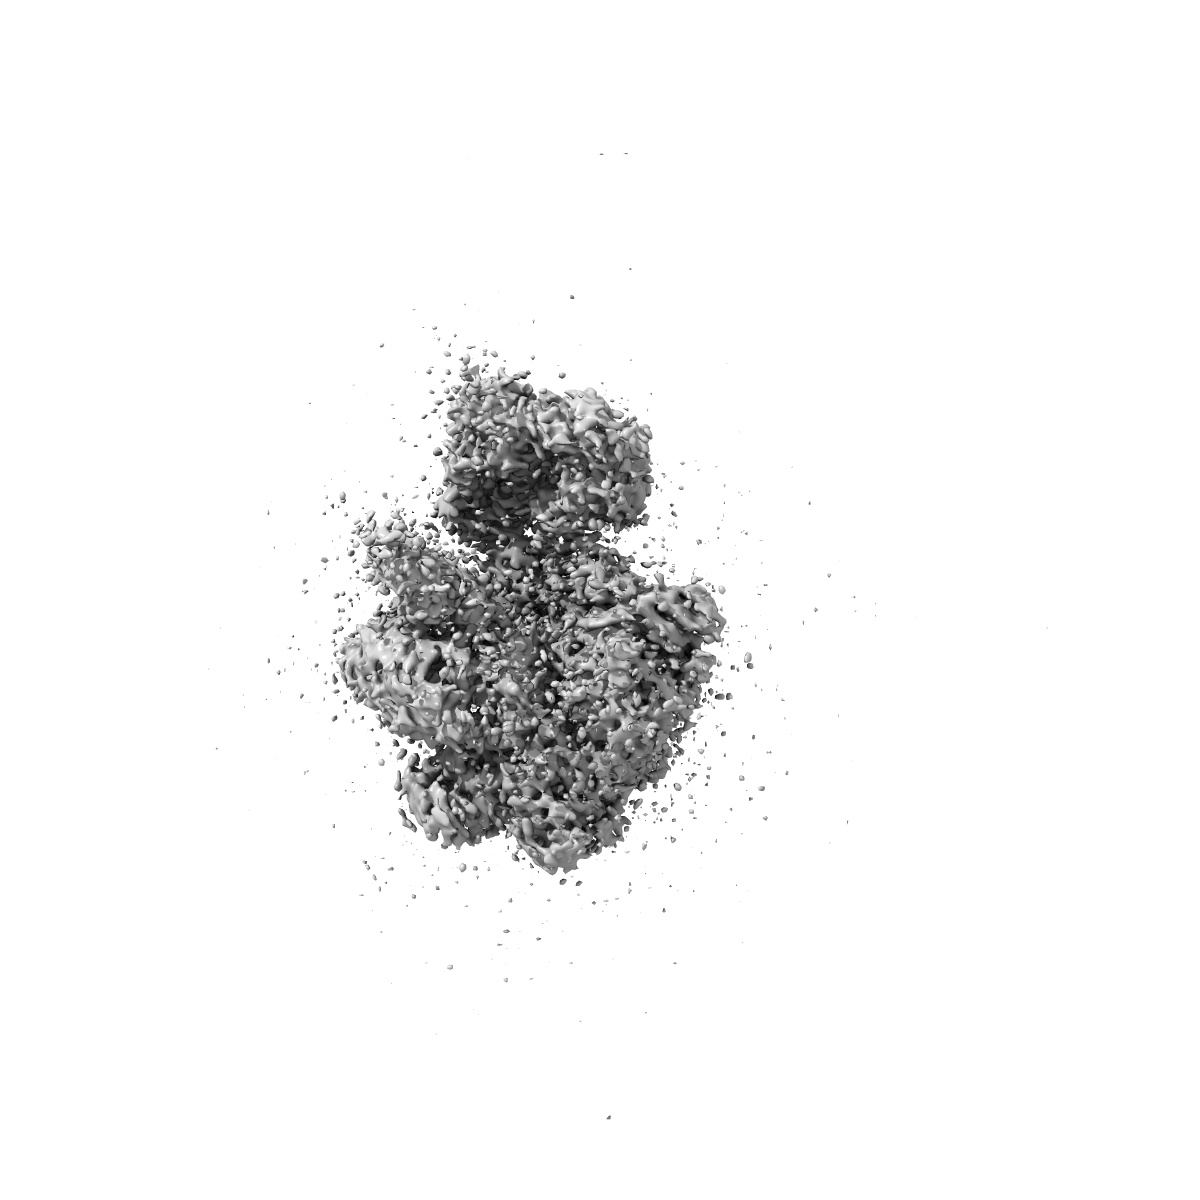

Monkeypox virus DNA replication holoenzyme F8, A22 and E4 complex in a DNA binding form

Sample: Monkeypox virus replication holoenzyme F8-A22-E4 complex with DNA duplex only

Structural basis of human mpox viral DNA replication inhibition by brincidofovir and cidofovir.